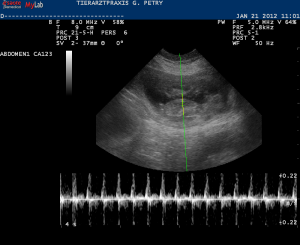

Hier sieht man einen Hundefötus, dessen Herzfrequenz mittels Doppler gemessen wird.